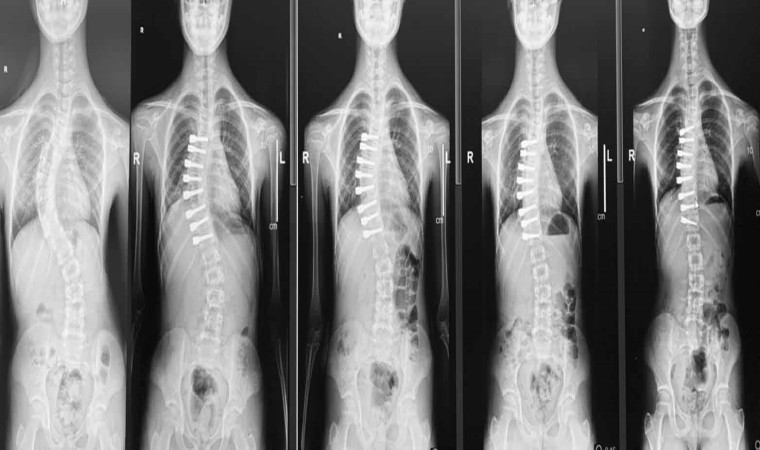

Ortopedi ve Tramvatoloji Uzmanı Doç. Dr. Tuna Pehlivanoğlu, çocuk hastalar için umut olan ipli skolyoz ameliyatını anlattı. Pehlivanoğlu, "Bu teknik devrim niteliğinde, çocukların büyümesine ve gelişmesine izin veren bir yöntem. Burada yaptığımız iş klasik ameliyattaki gibi sırttan büyük bir kesik yapmak değil. Göğüs boşluğuna kenardan ufak kesik yaparak vidaları kamera yardımıyla koyuyoruz. Araya da bir ip gerdiriyoruz. Gerdirmeyle eğriliği yani skolyozu düzeltiyoruz. Sonrasında çocuk büyüyerek kendi kendisini de düzeltiyor. Bu ameliyat eskiden tek bir taraftan yapılabiliyordu. Vidalar tek bir taraftan koyulabiliyordu. Biz bunu iki taraftan da yapılabilir hale getirdik" dedi.

Ortopedi ve Tramvatoloji Uzmanı Doç. Dr. Tuna Pehlivanoğlu, skolyoz hastası çocukların tedavisi hakkında konuştu. Genelde çocuklarda skolyoz hastalığının görüldüğünü belirten Pehlivanoğlu, 40 derecenin üzerindeki eğriliklere ameliyatla tedavi önerildiğini söyledi. Klasik skolyoz ameliyatında omurgaya arkadan yerleştirilen vidalar nedeniyle çocukların omurgalarında hareket engelinin meydana geldiğini ifade eden Pehlivanoğlu, tedavinin sonucunda çocukların büyüme ve gelişmelerinin durduğunu kaydetti. Ancak geliştirilen ipli ameliyat yöntemiyle skolyoz hastası çocukların büyüyüp gelişebileceğini belirten Dr. Pehlivanoğlu, ameliyatı uyguladıkları profesyonel sporcuların ve dansçıların da olduğunu aktardı. Ameliyat yöntemi hakkında bilgi veren Doç. Dr. Tuna Pehlivanoğlu, göğüs boşluğunun kenarından küçük kesik yaparak vidaların kamera yardımıyla koyulduğunu ardından da araya bir ip gerilerek skolyozu düzelttiklerini anlattı. Bu yöntemi göğüs boşluğunun iki tarafından da vida yerleştirerek uygulanabilir hale getirdiklerini söyleyen Pehlivanoğlu, eğriliği fazla olan çocuklara vidaların bir kısmının sağdan bir kısmının ise soldan yerleştirildiğini belirtti. Öte yandan tedavinin büyüme potansiyeli olan, büyümesi devam eden, eğriliği esnek olan ve genelde 60-65 dereceyi geçmeyen hastalara uygulandığını da aktardı.

Ameliyat yöntemini uygulamada dünyadaki öncülerden bir tanesi olduklarını ifade eden Pehlivanoğlu, "Burada yaptığımız iş klasik ameliyattaki gibi sırttan büyük bir kesik yapmak değil. Göğüs boşluğuna kenardan ufak kesik yaparak vidaları kamera yardımıyla koyuyoruz. Araya da bir ip gerdiriyoruz. Gerdirmeyle eğriliği yani skolyozu düzeltiyoruz. Sonrasında çocuk büyüyerek kendi kendisini de düzeltiyor. Bu ameliyat eskiden tek bir taraftan yapılabiliyordu. Vidalar tek bir taraftan koyulabiliyordu. Biz bunu iki taraftan da yapılabilir hale getirdik. Yani eğriliği daha fazla olan çocuklarda vidaların bir kısmını sağ taraftan, bir kısmını da sol taraftan koyuyoruz. Bu şekilde düzeltiyoruz. Eskiden ipli skolyozla bunu yapmak mümkün değildi. Biz dünyada ilk olarak bunu uygulayıp literatürde de yayınlayarak mümkün olduğunu gösterdik. Artık o çocuklarda ipli skolyozla tedavi olabiliyorlar. İpli skolyoz herkese uygulanmaz. İpli skolyozu uygulayabileceğimiz hastalar, büyüme potansiyeli olan, büyümesi devam eden, eğriliği esnek olan ve genelde 60-65 dereceyi geçmeyen hastalara uyguluyoruz" şeklinde konuştu.